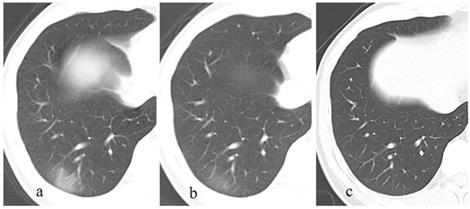

After discharge, all the pulmonary lesions were completely absorbed on the latest CT (Fig. 1-2), the duration of lesions from occurrence to disappearance was 31.6 ± 11.4 days (range: 5-50 days). Among different lesions, duration of GGO was the longest (mean: 29.8 ± 12.1 days, range: 5.0-50.0), which was significantly longer than that of fibrous strips (mean: 23.8 ± 9.5 days, range: 12.0-44.0) (p = 0.046) and consolidation (mean: 9.4 ± 3.6 days, range: 4.0-15.0) (p = 0.000).

Figure 1

A patient with a history of travelling to Wuhan recently, presents with fever and cough for 13 days. The initial chest CT at the first day after admission shows a patchy GGO in the right lower lobe (a). Subsequently (5 days later), this lesion is directly absorbed with decrease of extent and density (b). On the latest CT scan (18 days later), the lesion is completely absorbed (c).